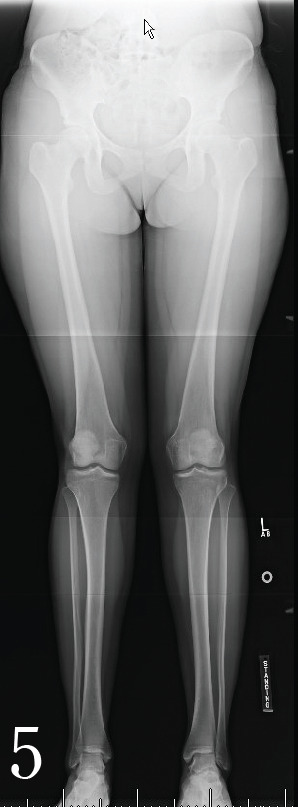

A 21-year-old woman’s collegiate Division I basketball player with a history of two prior left knee arthroscopies with partial lateral menisectomy presented with 1.5 years of left lateral knee pain and swelling nonresponsive to conservative measures. Standing radiographs demonstrated 8° of valgus alignment (Figure 5) and MRI revealed a chondral defect on the lateral femoral condyle. The patient was indicated for a DFO.

Figure 5.

Long Leg AP. There is 3° of valgus angulation of the mechanical axis on the right and 2° of valgus angulation on the left.